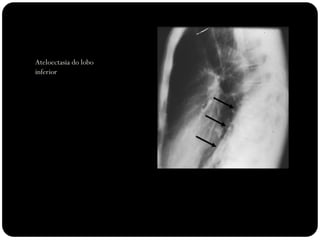

Atelectasia lobo

inferior direito

Observar:

Atelectasias de lobos

inferiores deslocam

o hilo posterior e

medialmente;